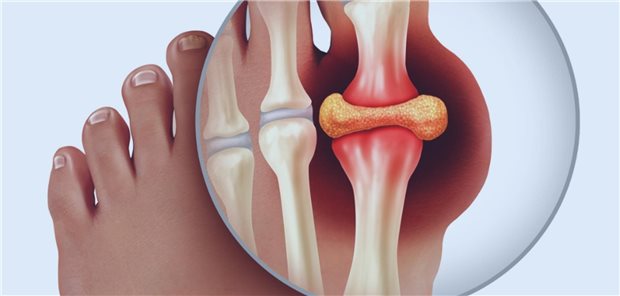

„Patienten mit Gicht zeigten ein überschießend erhöhtes Risiko für eine breite Palette kardiovaskulärer Erkrankungen, und zwar über den Bereich atherosklerotischer Krankheiten hinaus“, resümieren Ferguson et al. ihre Studienergebnisse. Die höchsten Risiken hätten Frauen und jüngere Patienten getragen.

© abhijith3747 / stock.adobe.com

Inzidenz von zwölf Erkrankungen steigt

Gicht erhöht das kardiovaskuläre Risiko breit gestreut

Autoren und Autorinnen weisen darauf hin, dass kristallinduzierte entzündliche Gelenkerkrankungen sich zwar typischerweise in Schüben manifestieren, aber auch persistierende Verläufe möglich sind. Es sollten nicht nur aktuell Beschwerden bereitende Gelenke, sondern auch typische Prädilektionsstellen wie das Großzehengrundgelenk bei Gichtverdacht, Knie und Handgelenke bei CPPD und die Schultern bei BCPD untersucht werden.

© wildpixel / Getty Images / iStock

Diagnostik bei Kristallarthropathien

Neue Praxisleitlinie zur Bildgebung bei Gicht & Co.